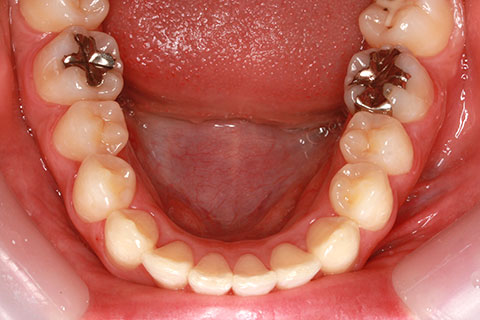

ハーフリンガル矯正3:上の歯のみ舌側矯正で治療(矯正期間24ヶ月)

治療前

治療中(開始直後)

治療中(開始半年後)

治療後

- 年齢・性別

- 25歳女性

- 治療期間

- 2年0ヶ月

- 抜歯

- 上下4番抜歯

- 治療費

- 110万円

- 治療内容

- 施術の副作用(リスク)

- 表側矯正と比較して、力学的な操作性が複雑なため、ボーイングエフェクトを起こしやすい。